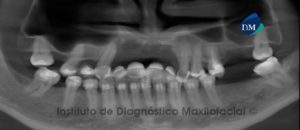

Paciente femenina de 51 años de edad que es referida para el estudio imagenológico previo a la colocación de implantes dentales. A la evaluación de